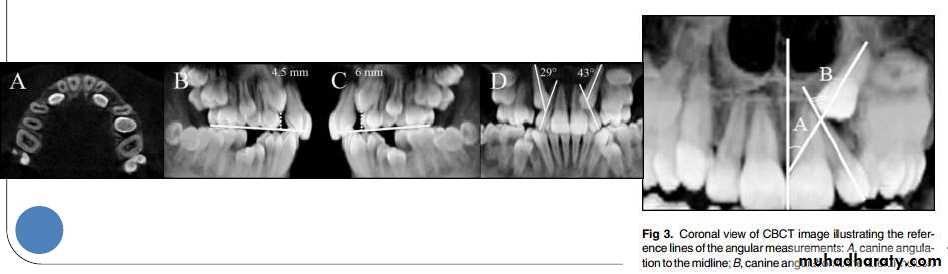

A study was done by Ali Alqerban et al AJODO March

2015, to compare 3D CBCT images of unilaterally

impacted canines with the normal contralateral sides,

and to detect possible radiographic factors involved in

maxillary canine impaction.

Prediction of the probability of canine impaction based

on CBCT was excellent. The canine angulation to the

lateral incisor on the coronal view, the canine cusp tip to

the occlusal plane on the sagittal view, and the canine

crown position were the strongest predictors based on

the CBCT radiographs and may help orthodontists to

identify the probability of impaction for optimally timing

the intervention.